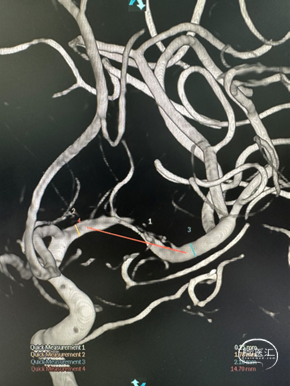

DSA

左侧大脑中动脉重度狭窄,近端:1.78mm,远端:2.18mm,最窄:0.25mm,长度:14.70mm,狭窄率约:89%。